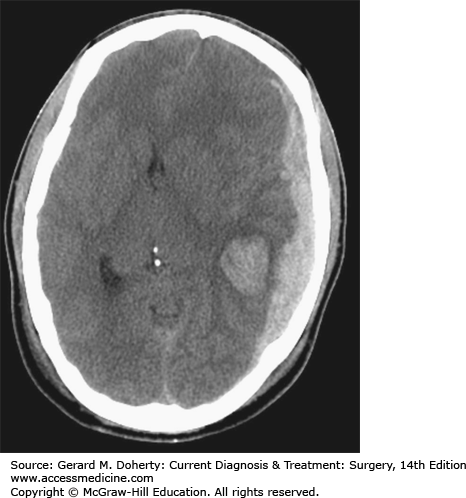

Acute subdural hematoma with an associated intraparenchymal hemorrhage after head trauma in a 25-year-old patient.

Doherty GM. CURRENT Diagnosis & Treatment: Surgery, 14e; 2015 Available at: http://accessmedicine.mhmedical.com/ViewLarge.aspx?figid=71524676&gbosContainerID=0&gbosid=0 Accessed: January 30, 2018